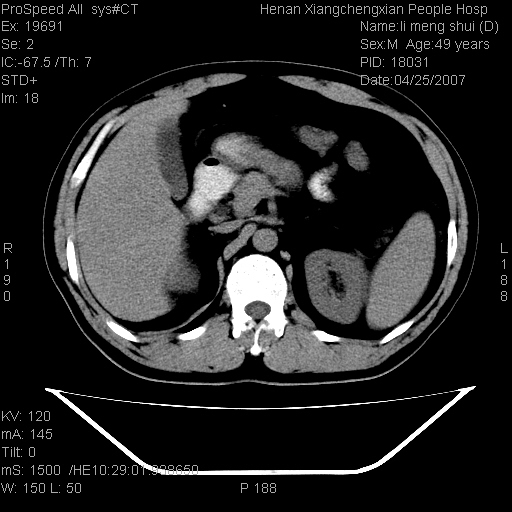

| 患者,男,49岁, 腹疼伴恶心\\呕吐20天,20天前无明显诱因出现右上腹部疼痛,钝疼,无放射,伴恶心\\呕吐,不伴发热.患者不愿增强. b超:肝脏右叶实性占位. ct:肝脏右叶可见一巨块状圆形低密度影,大小约93mm*84mm,其内可见点状高密度影,胆囊、胰腺、脾脏大小、形态及密度未见异常,腹膜后间隙未见肿大淋巴结影。 印象:肝脏右叶巨大肿块,性质待定,建议增强并穿刺活检进一步确诊。 ct平扫: ![]() ![]() ![]() ![]() ![]() ![]() ![]() ![]() ![]() ![]() ![]() ![]() ![]() ![]() ![]() ![]() ![]() 肝脏右叶肿块ct引导下穿刺活检术 患者于16时05分仰卧于ct检查台上,首先行肝脏ct扫描确定进针位置、深度、角度。在局麻下行ct引导下肝脏右叶肿块穿刺活检术。常规消毒、铺巾、局麻。在ct引导下使活检针经右侧腋中线、第9肋间隙垂直胸壁进针90mm,针头进入病变预定位置。在病变预定位置多点、多方向抽取小米样病变组织多块,涂片五张送病理检查。术后穿刺点局部无出血,未出现腹腔积液等并发症。术中及术后患者生命体征稳定,手术于17时10分成功完成。患者安返病房。 穿刺片 ![]() ![]() ![]() ![]() ![]() ![]() ![]() ![]() ![]() ![]() ![]() ![]() ![]() ![]() ![]() ![]() 病理结果肝细胞癌 ![]() 原贴地址:http://www.radinet.com.cn/forum_view.asp?forum_id=4&view_id=24130 ok |